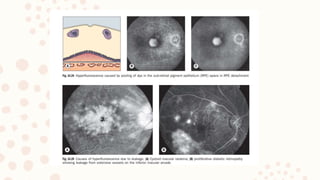

9.FLUORESCEIN ANGIOGRAPHY

FFA is a very useful tool in diagnosing macular disorders

– e.g. diabetic maculopathy, CSR and can reveal the functionality of the lesion